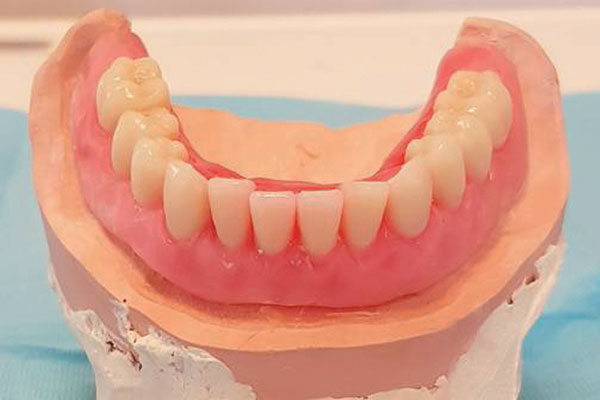

L’overdenture è tra le soluzioni preferite dai pazienti che cercano una protesi più stabile rispetto a quella rimovibile, ma per varie ragioni preferiscono evitare l’intervento di implantologia tradizionale.

È una protesi completamente rimovibile e personalizzata, la cui stabilità è garantita dal posizionamento sull’arcata da riabilitare di due o quattro impianti collegati tra loro eventualmente da una barra. La protesi risulterà stabile perché agganciata proprio agli impianti o alla barra con attacchi particolari.

La soluzione permette di eliminare il ricorso alle paste adesive, riduce il rischio di infiammazione alle gengive conseguente all’utilizzo delle protesi rimovibili ed è più confortevole. L’overdenture per l’arcata superiore, infine, è priva del palato artificiale, spesso percepito come un corpo estraneo.